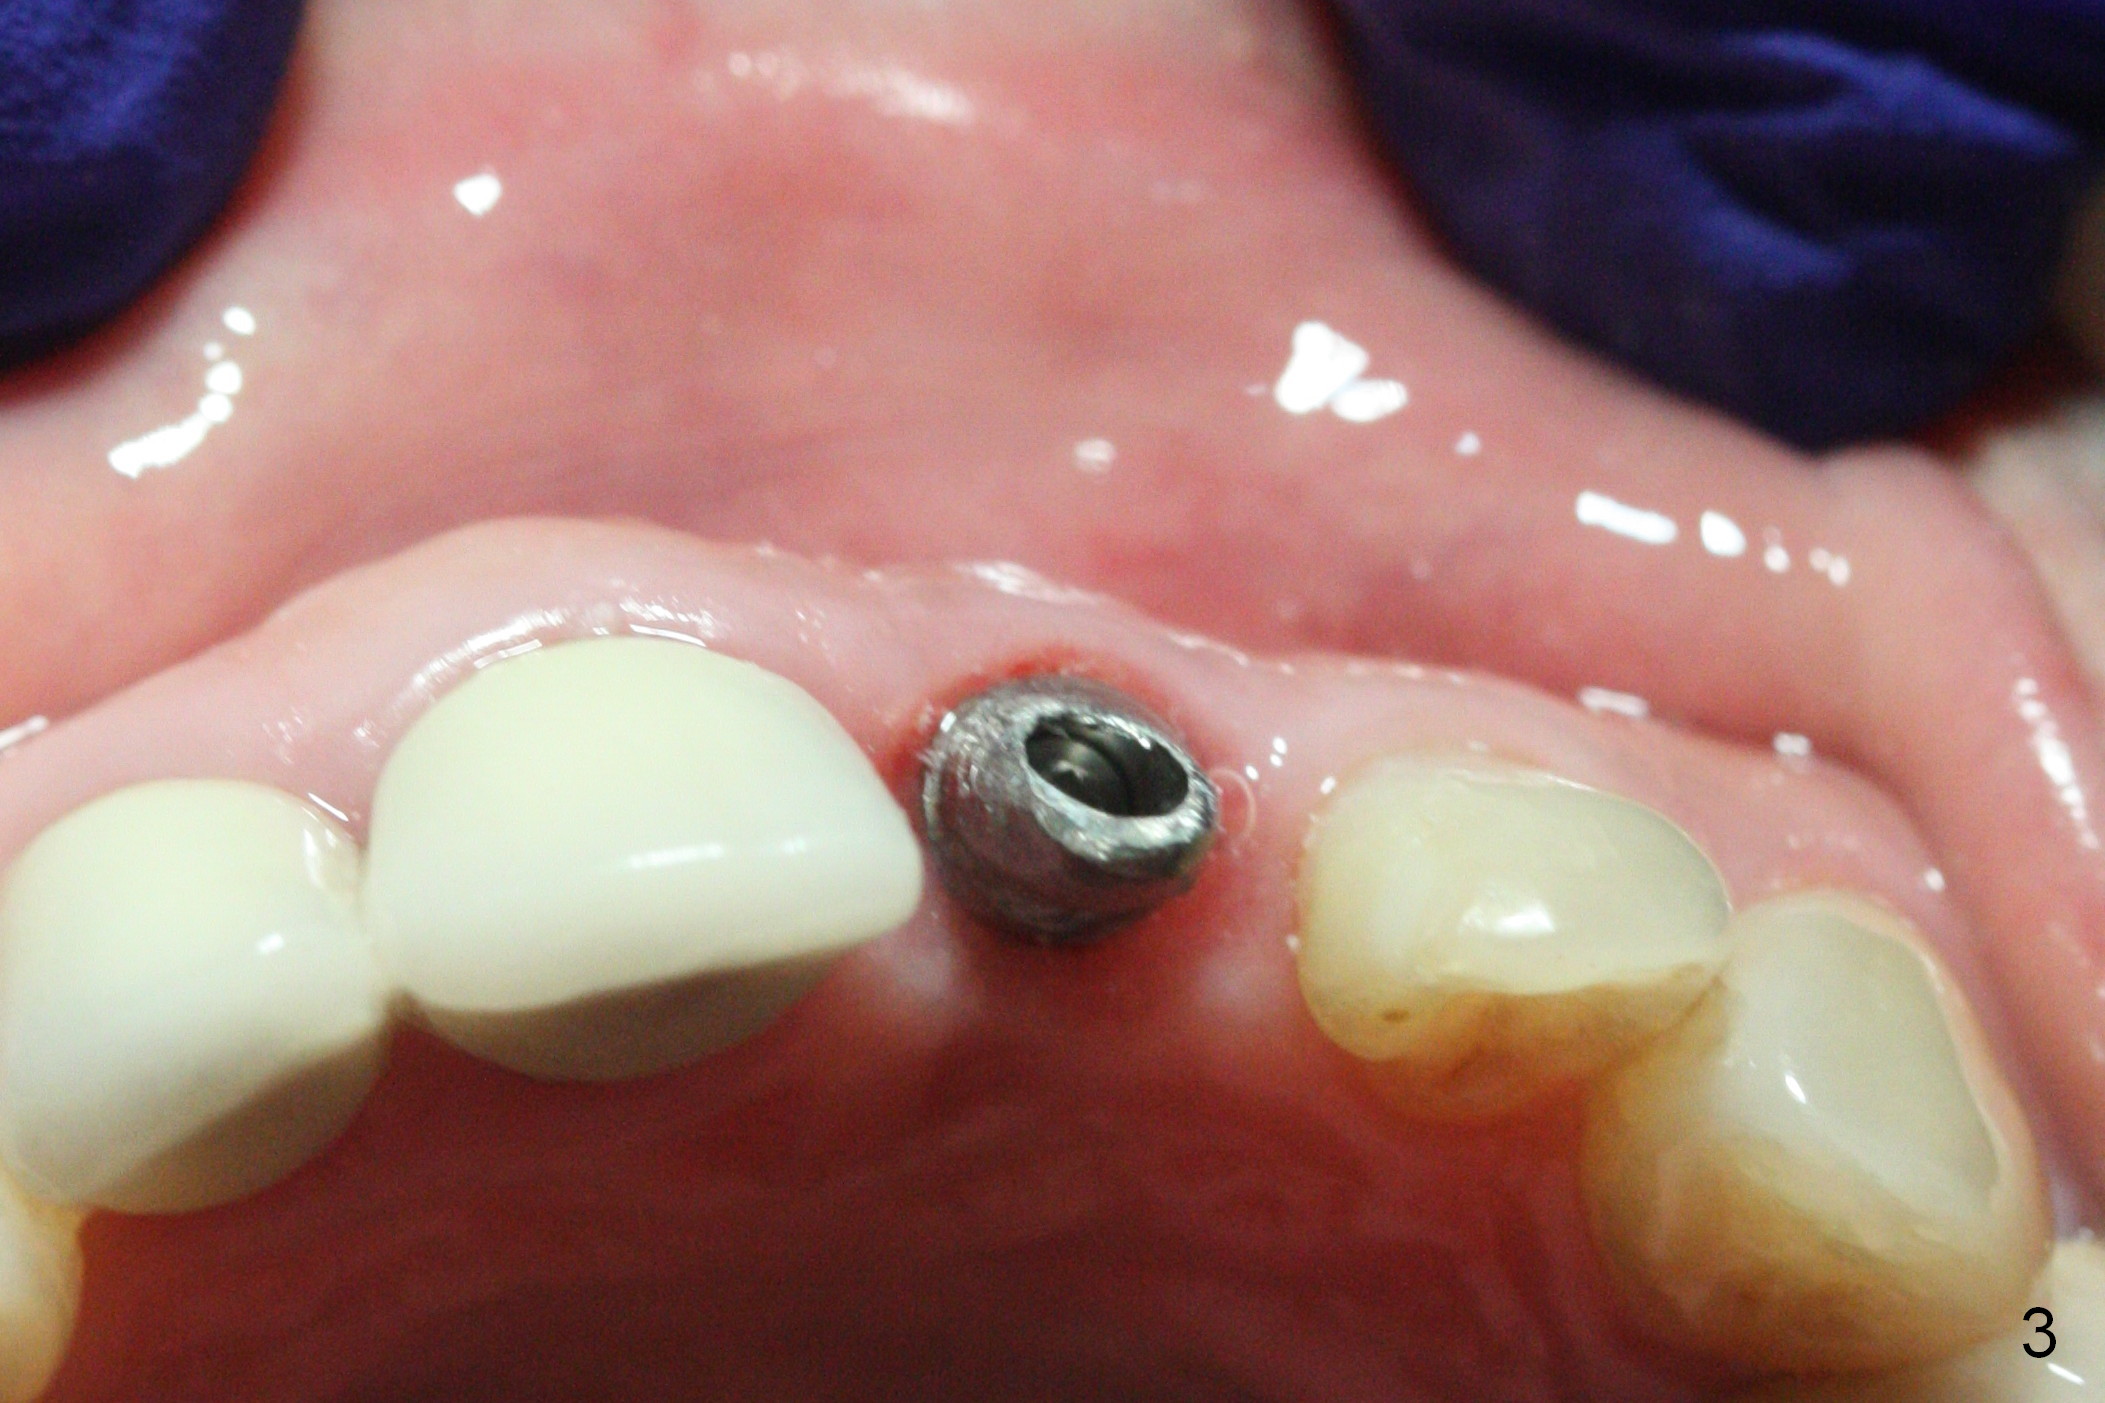

When a permanent crown (Fig.1 C) is seated 5 months postop, it looks too long and bulky (as well as metal show through cervically), which is in turn due to buccal placement of the crown (Fig.2) and abutment (Fig.3).  By mistake, abutment is changed from 4.5x15°, 3 mm cuff to 4.5x15°, 2 mm cuff (Fig.4-6); the profile appears to improve.  After prep (buccoincisal (Fig.4 ^) and linguoincisal), impression is taken.  The gold coating in the buccocervical area is untouched so that there should be no or minimal metal show through.  Please make a new crown as cosmetic as possible (not too bulky, especially buccocervical).  If you feel that the result will be the same as before, return the case.  The angled abutment may be changed 25°.  In fact the new crown looks better.